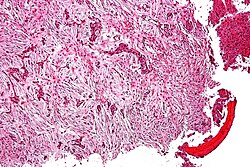

Microscopic

Features:

- Fibrosis.

- +/-Giant cells with round to oval nuclei and nucleoli.[10]

- Bone unaffected by tumour - increased numbers of the following:

- Multinucleated cells (osteoclasts).

- Mononuclear cells around the bony trabeculae (osteoblasts).

DDx:

- Giant cell tumour of bone and other giant cell lesions.